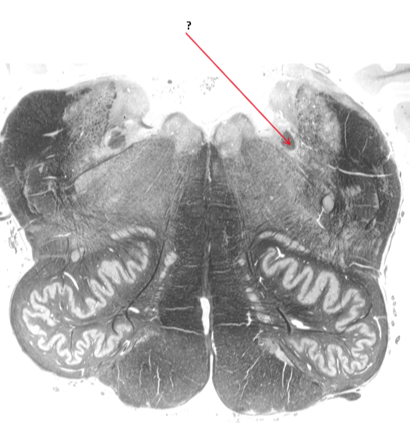

Name this and state its function.

Neurotransmitters involved?

Nucleus Tractus solitarius(NTS).

Name this.

Medial vestibular nuclei.

Inferior vestibular nucleus.

Name and state its function in each hemisphere.

Arcuate fibres.

Left hemisphere:

Right hemisphere: